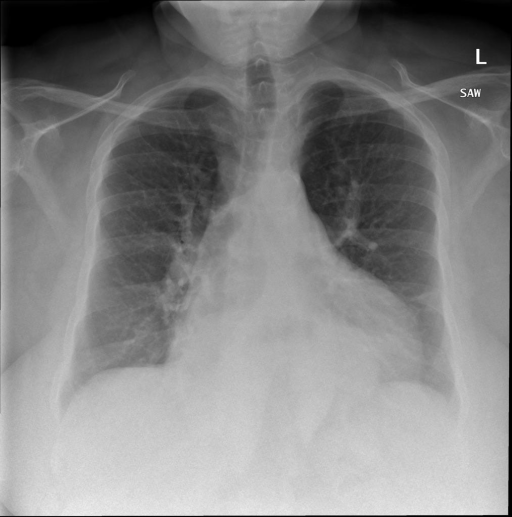

Indiana Dataset [19]: Set consists of 7284 CXRs, both frontal and lateral images with disease annotations, such as cardiomegaly, pulmonary edema, opacity or pleural effusion. Indiana Set is collected from various hospitals affiliated with the Indiana University School of Medicine. The set is publicly available through Open-i SM, which is a multimodal (image + text) biomedical literature search engine developed by U.S. National Library of Medicine. A typical example of a normal CXR (left) and a CXR with cardiomegaly abnormality (right) is shown in Fig. 1. Visually, it can be observed that the heart in the cardiomegaly example is quite big compared to that of the normal CXR.

Figure 1: An example of Normal CXR (left) and an example of a cardiomegaly CXR (right) from Indiana dataset. The pathology in the right CXR can be easily distinguished from the abnormal size and shape of the heart. -